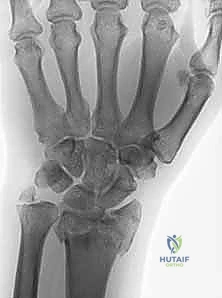

- الأشعة السينية (X-rays): بأوضاع متعددة لتقييم زوايا الكسر ومقدار الانهيار العظمي.

- الأشعة المقطعية (CT Scan) مع إعادة البناء ثلاثي الأبعاد (3D Reconstruction): وهي خطوة إلزامية في الكسور المعقدة. تتيح للدكتور هطيف رؤية كل شظية عظمية داخل المفصل بدقة متناهية والتخطيط للعملية الجراحية قبل دخول غرفة العمليات.

لفهم قيمة "الصفيحة الجسرية"، يجب أن نقارنها بالبدائل المتاحة. في حالات التفتت الشديد (حيث يكون العظم أشبه بالزجاج المهشم)، تفشل العديد من الطرق التقليدية.

| أسلاك كيرشنر (K-wires) | أسلاك معدنية تخترق الجلد لتثبيت العظم. | كسور الأطفال أو الكسور الأقل تعقيداً. | لا توفر ثباتاً كافياً للكسور عالية الطاقة، خطر العدوى. |

| الصفائح العادية (Volar Plates) | صفيحة تثبت مباشرة على العظم المكسور. | الكسور التي تحتوي على قطع عظمية كبيرة يمكن تثبيتها. | تفشل إذا كانت الشظايا صغيرة جداً ولا تتحمل البراغي (خطر ارتخاء البراغي). |

| الصفيحة الجسرية (Bridge Plating) | صفيحة طويلة تمتد من الساعد وتعبر المفصل لتثبت في عظام اليد. | الكسور شديدة التفتت، فقدان العظم، والإصابات المتعددة. | يتطلب جراحة ثانية لإزالة الصفيحة بعد التئام العظم (بعد 3-4 أشهر). |